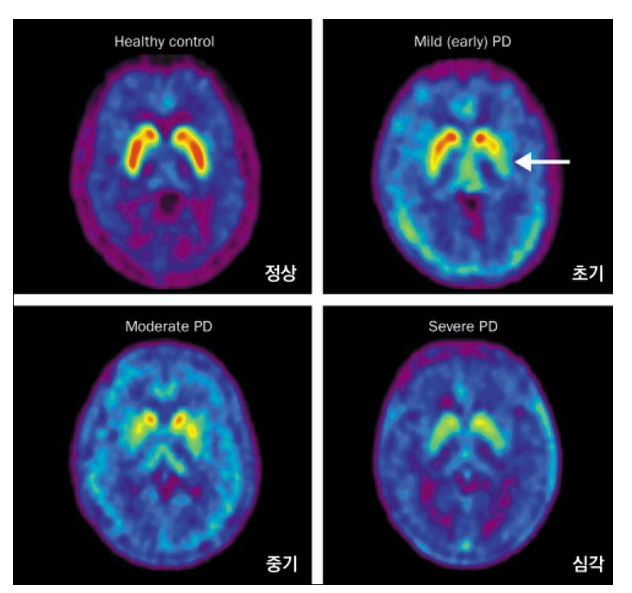

- 도파민 운반체 영상(DaTscan, FP-CIT PET): 도파민 결핍 여부 확인

초기 증상과 진행 속도

초기에는 한쪽 손의 떨림, 다리 끌기, 글씨 작아짐, 후각 저하 등 매우 미세한 증상으로 시작되며, 노화로 착각하기 쉬워 조기 발견이 어렵습니다. 도파민 세포가 약 60~80% 파괴된 후에야 뚜렷한 증상이 나타납니다.